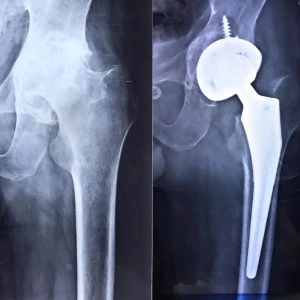

Total Hip Replacement (THR), also known as Total Hip Arthroplasty, is a surgical procedure performed to relieve pain and restore function in patients with severe hip joint damage. This procedure involves replacing the damaged hip joint with an artificial implant, significantly improving the patient’s quality of life.

5. Implant Placement: The artificial joint components are placed in the hip socket and femur.

6. Closure: The incision is closed, and a drain may be placed to remove excess fluids.